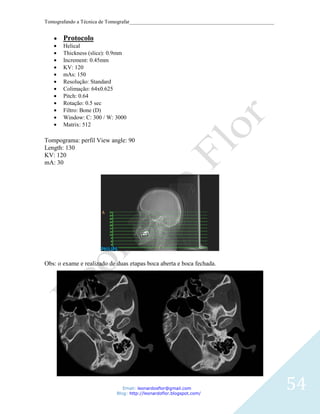

Protocolo

Helical

Thickness (slice): 0.9mm

Increment: 0.45mm

KV: 120

mAs: 150

Resolução: Standard

Colimação: 64x0.625

Pitch: 0.64

Rotação: 0.5 sec

Filtro: Bone (D)

Window: C: 300 / W: 3000

Matrix: 512

Tompograma: perfil View angle: 90

Length: 130

mA: 30

Obs: o exame e realizado de duas etapas boca aberta e boca fechada.